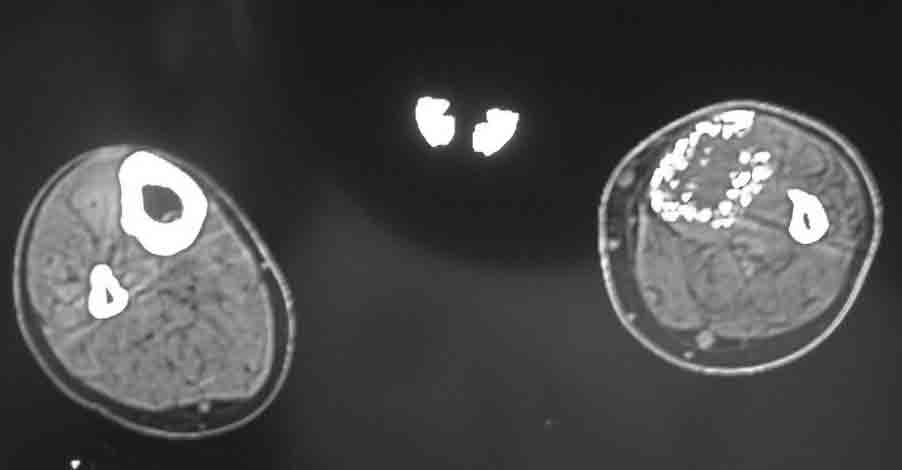

下图 踝关节感染骨髓炎改变。

下图 CT显示,左胫骨延长区骨膜下成骨,骨质稀疏。